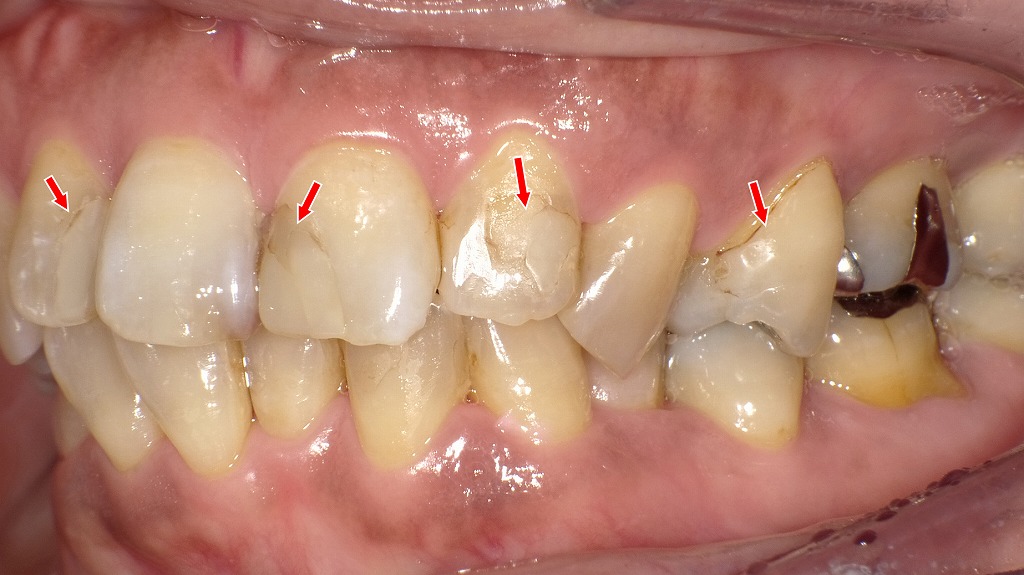

この画像は左下第2小臼歯(5番)を示しています。赤い矢印で示された歯には、CAD/CAMインレー(ハイブリッドセラミックインレー)が装着されています。

🦷 観察ポイント

- 詰め物の素材

銀歯ではなく、歯とほぼ同じ色調の白いインレーが確認できます。

これはレジンとセラミックを混合したハイブリッドセラミック製で、CAD/CAMシステムにより設計・削り出されたものです。 - 隣接面の適合性

隣の銀歯(左下第1大臼歯)との接触点も適切で、段差や隙間が見られません。

デジタル設計による高い精度で作製されていることが分かります。 - 形態・色調

咬合面の形態が自然で、歯の丸みやツヤも周囲の天然歯とよく調和しています。

わずかに明るめの色ですが、審美的に非常に自然な印象です。

💬 臨床的評価

左下5番のCAD/CAMインレーは良好に適合しており、辺縁漏洩や咬合不調の兆候は認められません。

清掃状態も良好で、プラーク付着や着色もほとんどありません。

保険適用の白い詰め物として機能的・審美的に安定しており、長期経過も期待できます。